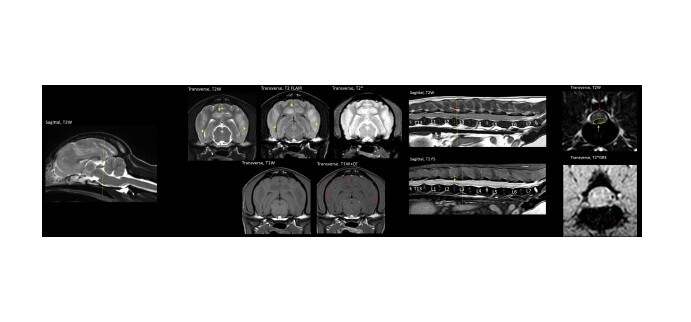

| ▲ 1살 미니어처푸들 발작 증상, MRI로 뇌염 확인(사진 좌), 3살 말티즈 후지마비 증상, MRI로 출혈을 동반한 추간판 탈출증 확인되어 수술 진행 |

MRI는 수분 함량이 높은 연부조직을 정밀하게 관찰하는 데 특화된 검사다. 뇌수두증, 뇌수막염, 뇌종양, 원인 불명의 발작과 같은 뇌·신경계 질환, 디스크 탈출증(IVDD), 척수연화증, 척수종양 등 척추 질환에서는 MRI가 사실상 필수적인 진단 도구로 활용된다.